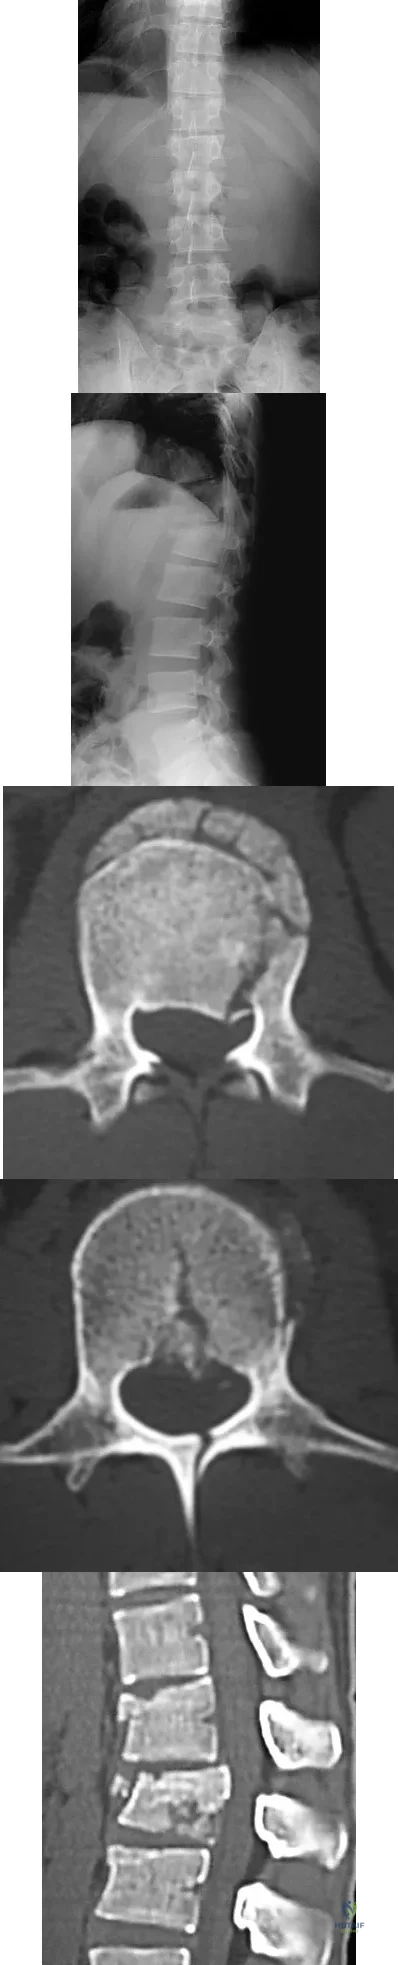

Question 47

An 18-year-old collegiate basketball player has had a 3-month history of activity-related back pain. She describes isolated low back pain without radiation that increases with training and playing basketball. Her pain resolves with rest. Physical therapy for 6 weeks has failed to provide relief. An axial CT scan is shown in Figure 17a, and Figures 17b and 17c show sagittal CT reconstructions through the right and left lumbar facets, respectively. Further management should consist of which of the following?

Explanation